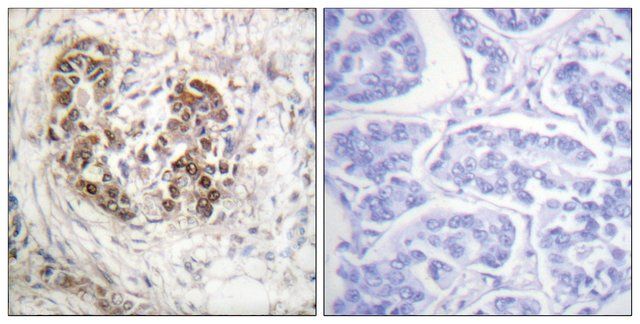

The antiserum was produced against synthesized peptide derived from human IRS-1 around the phosphorylation site of Ser794.

Immunogen Range: 760-809

| technique(s) | ELISA: 1:40000 immunohistochemistry: 1:50-1:100 |